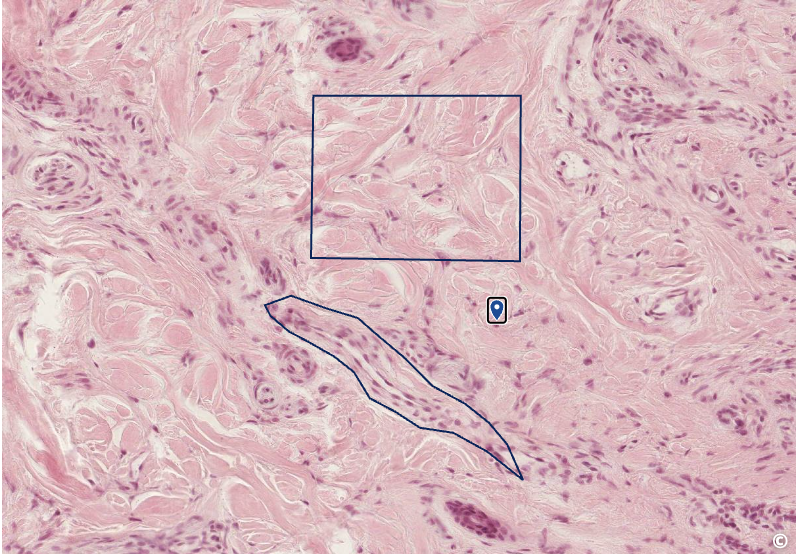

<p>identify CT</p>

identify CT

dense irregular